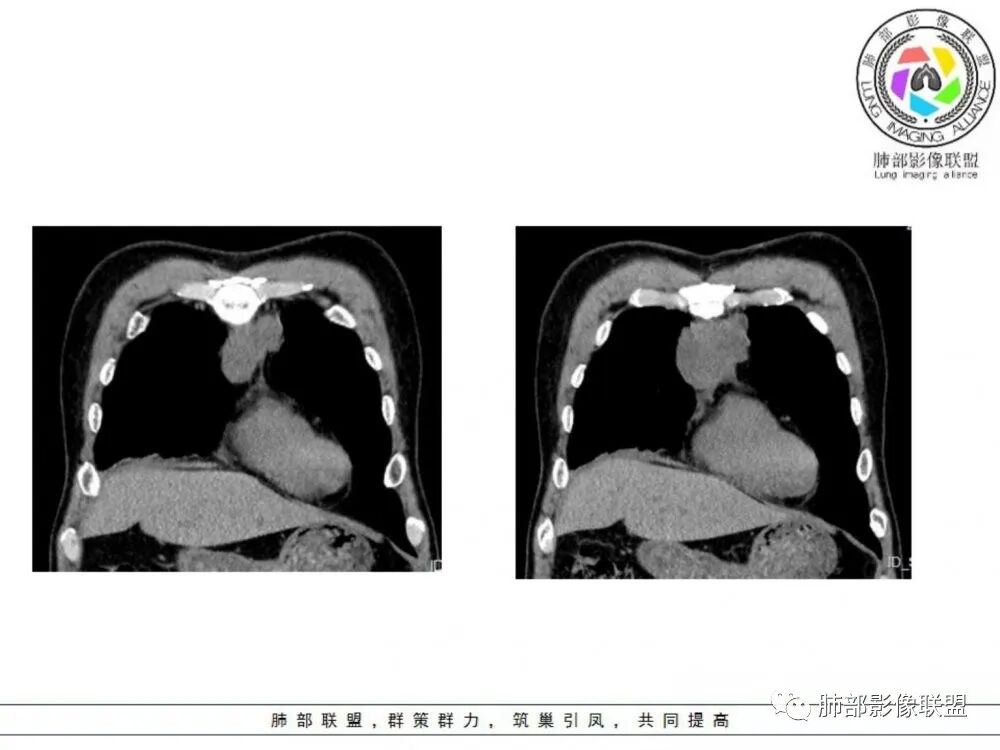

男性患者,65岁,前胸后背疼痛一个月。影像学前上纵隔分叶状的软组织肿块,肿块形态怪异,偏软,位于大血管间隙前,并有向血管后间隙发展的趋势,平扫CT值为40左右,增强扫描中心部未见强化,周围轻度的强化,约为50左右。前上纵隔的疾病谱包抬胸廓内甲状腺肿、胸腺瘤/癌、畸胎瘤、淋巴瘤。少见的心包囊肿或支气管囊肿。根据肿块的形态及强化特点,首先还是排除了胸内甲状腺肿及胸腺来源的肿物,这类的肿物强化比较明显。畸胎瘤成分比较复杂,具有软组织钙化或者脂肪类的组织,这个肿物虽然在平扫的时候好像有斑点状的钙化灶,但是总体成分还是比较单一,所以还是排除畸胎瘤的诊断。所以这样的情况是考虑:淋巴类的肿瘤,注意排除心包的囊肿或支气管来源的囊肿。

老年男性患者,前膈软组织肿块,边缘轮廓不光整,边界似乎尚清晰,内见小点状钙化灶,平扫密度欠均匀,增强后轻度强化表现,边缘有些斑片状的高强化区。综合考虑胸腺瘤或胸腺鳞癌,神经内分泌癌强化弱了一些。患者年龄较大,生殖细胞肿瘤不考虑,淋巴瘤血管包绕不够,可能性不大

老年男性患者,前膈软组织肿块,边界似乎尚清晰,内见小点状钙化灶,平扫密度欠均匀,增强后轻度强化表现,边缘有些斑片状的高强化区,考虑胸腺瘤或胸腺癌。

老年男性患者,前膈软组织肿块,边缘轮廓较光整,未见明显分叶,部分边界与周围分界不清,内见小点状钙化灶,平扫密度欠均匀,增强后病灶轻度不均匀强化。老年人,考虑胸腺瘤或胸腺鳞癌,神经内分泌癌待排。鉴别淋巴瘤,后者边缘可见分叶。强化多均匀。

中老年男性,前纵隔占位,基本居中,向两侧生长;边缘膨隆分叶,部分边界不清,增强不均匀轻中度强化,坏死区边界不清;周围多发增大淋巴结,考虑恶性。主要在胸腺癌、胸腺瘤、淋巴瘤之间鉴别。病灶偏软,有钻缝样生长,这些征象偏向于淋巴瘤。但此例老年患者,病灶内有点状钙化,缺乏结节堆砌感,倾向胸腺癌诊断。